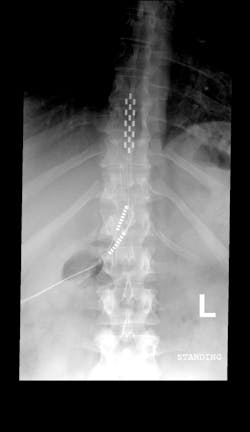

In May 2011, it was reported that a neuroscientist in Kentucky had successfully used electric spinal stimulation in getting a paralyzed patient to stand. The patient had even gained some control of his bladder, bowel, and sexual functions, even when the electrodes were turned off. So the FDA then gave approval for Neuroscientist Susan Harkema to try the same technique in four other paralyzed patients.

The circuitry of the lower spinal cord is impressively sophisticated. Neuroscientists believe that the brain merely provides high-level commands for major functions, like walking. Then the dense neural bundles in the lower spinal cord take over the details of coordinating the muscles, allowing the brain to focus on other things. That division of labor is what lets you navigate a party and focus on the conversation rather than on your steps. After a spinal-cord injury, damage prevents the high-level signal from the brain from reaching the neurons below. Yet those neural bundles remain intact and are just waiting to receive a signal to start the muscles working. Stimulating the lower spinal cord with electrodes can awaken that circuitry and get it functioning, astonishingly, without instructions from the brain...(IEEE Spectrum)